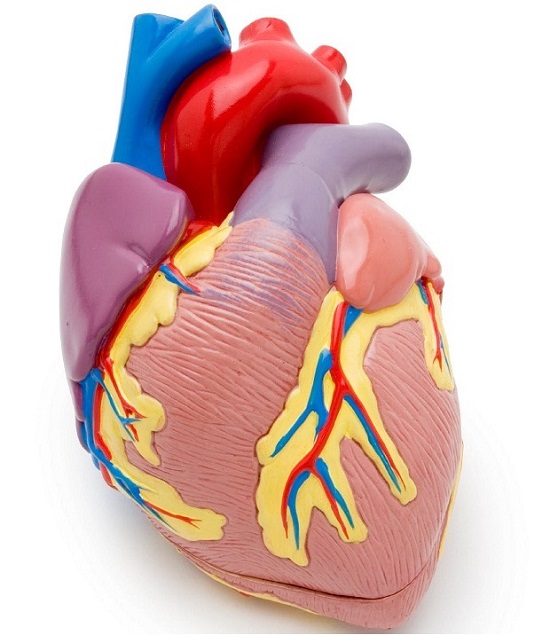

Анатомия здорового сердца: фотографии и иллюстрации